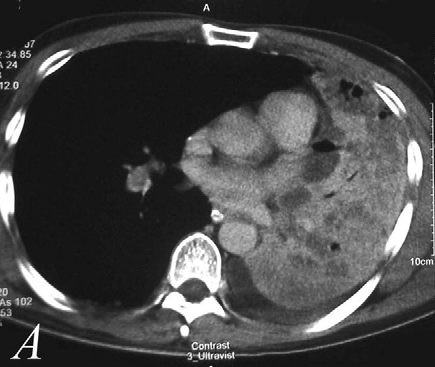

Ən çox metastaz verdiyi orqanlar - sümüklər, qaraciyər, böyrəküstü vəzi və beyindir.

- Uzaq metastazaları təyin etmək üçün ilk növbədə abdominal KT (böyrəküstü vəzə və qaraciyərə yayılmanı qiymətləndirmə) edilir, sümüklərə və beyinə metastazı yoxlamaq üçün PET-KT tətbiq edilir.